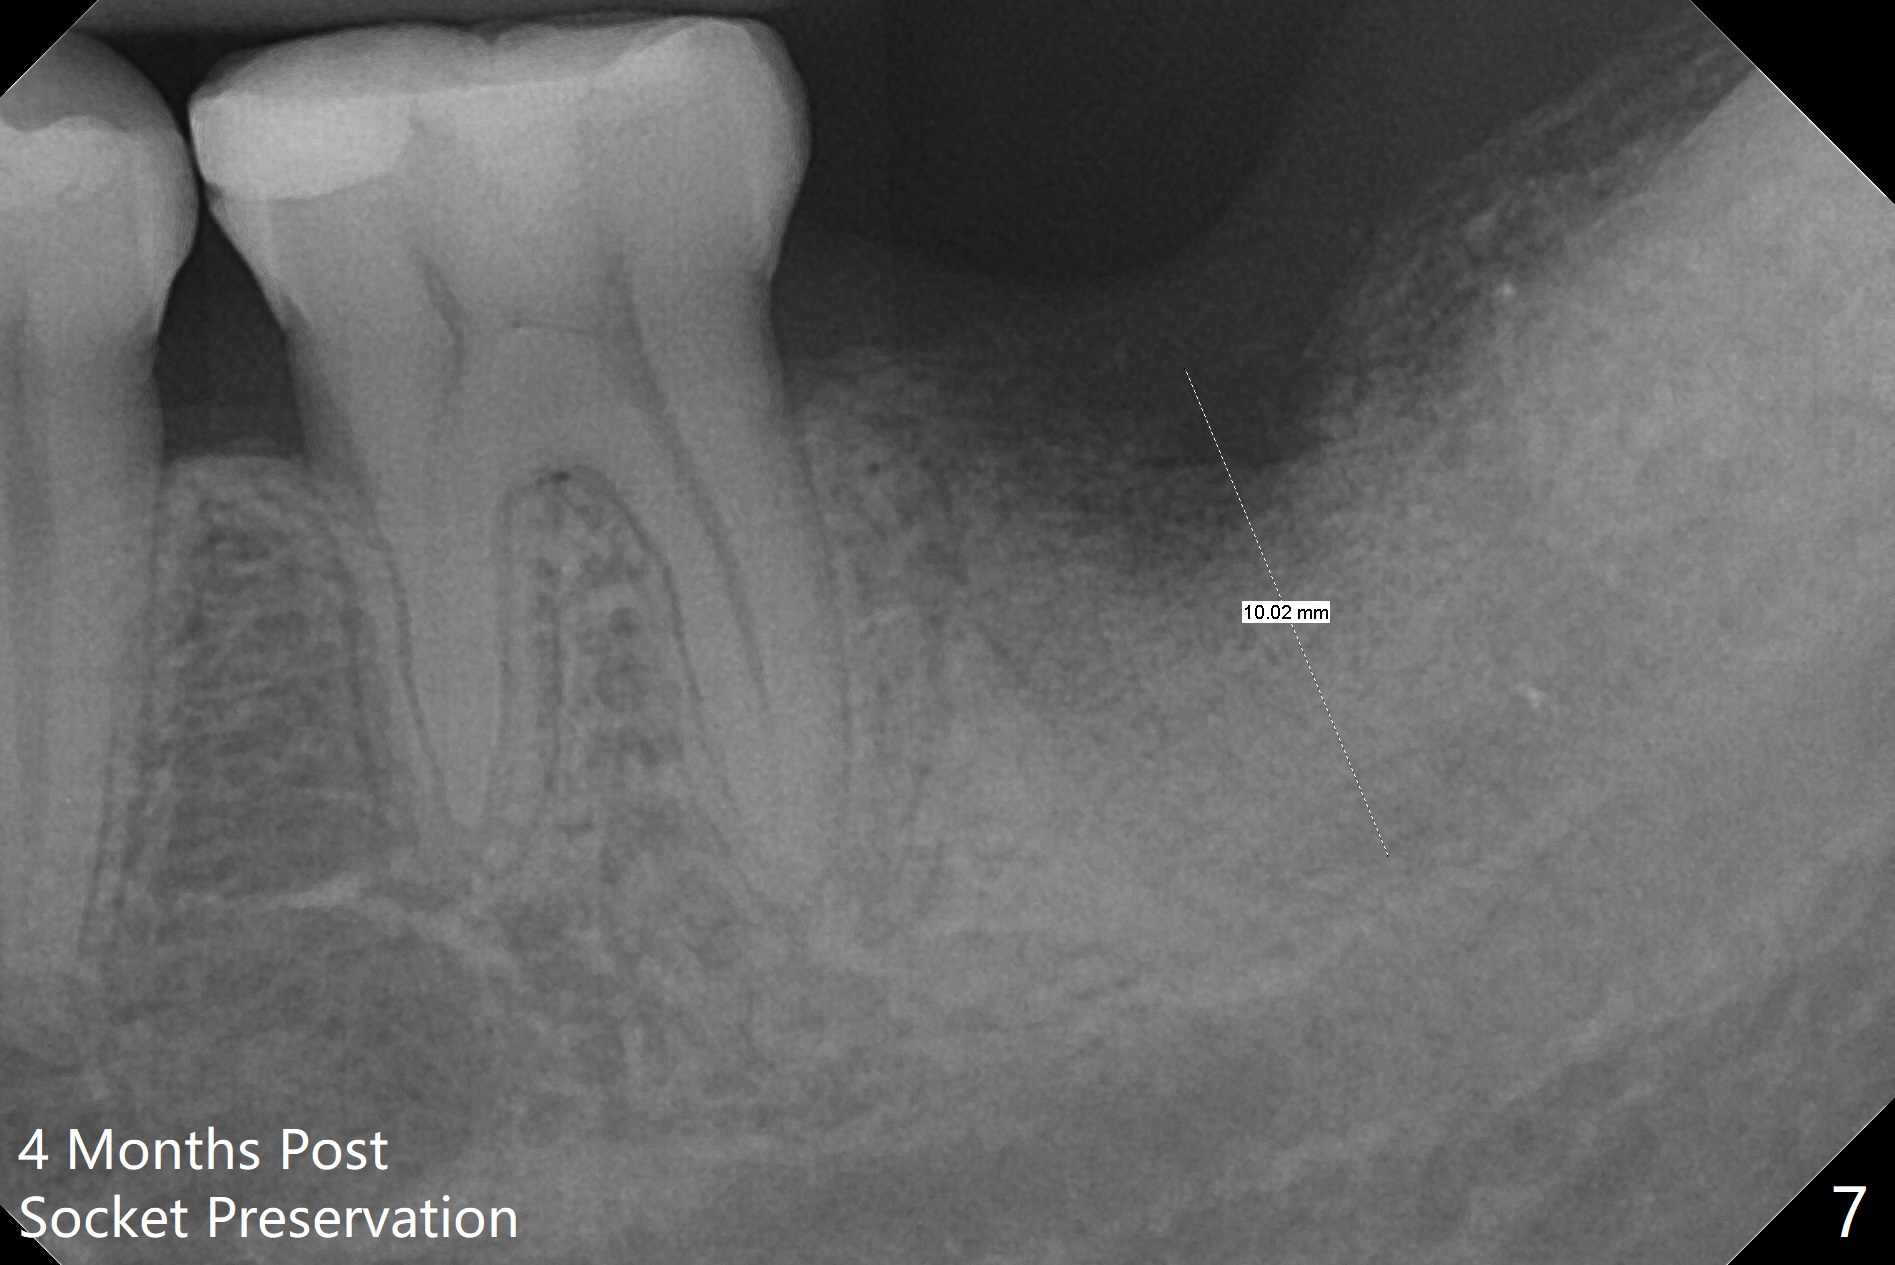

The patient with chronic buccal abscess at #31 is nervous. After extraction, a 7x11 mm tapered implant drops into the single socket, which is close to the Inferior Alveolar Canal (Fig.2). The bottom of the socket is sensitive to manipulation (explorer) after infiltration anesthesia. A 8x14 mm tapered tap is placed without binding, neither is a 8x14 mm cylindrical implant. The implant stability does not increase when Vera (.2-1.0 mm) or Vanilla (.5-1.0 mm) Graft is placed. Socket preservation is finished with Collagen plug and 6-month membrane (Fig.3,4).